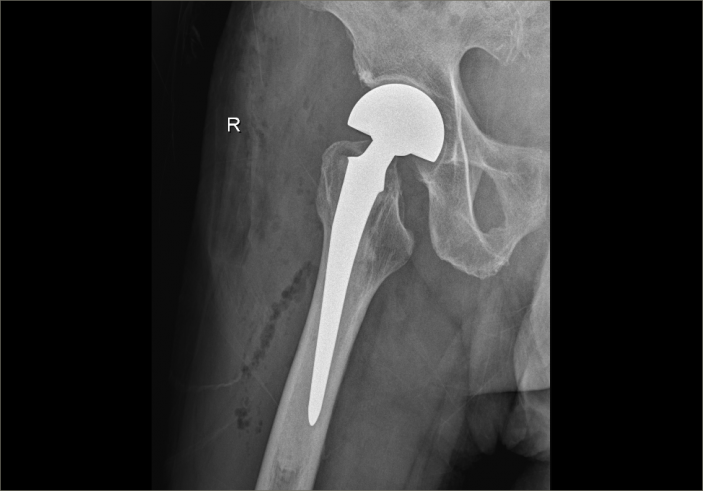

經過内科對症治療後,患者病情穩定,吳主任帶領團隊抓住時機,在麻醉科的配合下,果斷爲其施術。根據術前拟定方案按部就班實施手術,娴熟地切開組織、修整股骨近端、安裝骨柄假體和雙動股骨頭、複位髋關節,并細心檢查髋部活動度良好、雙下肢等長後,縫合切口順利完成手術。因術前準備充分,整個術程一氣呵成,既縮短手術時間,也減少術中出血,有效降低手術給患者帶來的傷害。